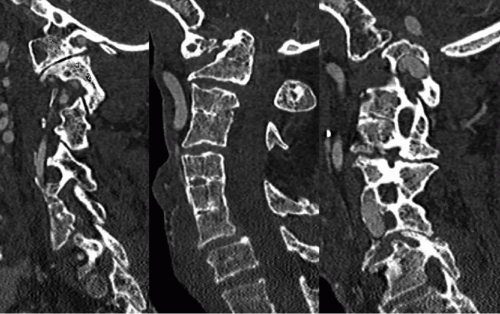

Carefully assess vertebral arteries for any anatomic variation and to determine safe zones for exposure and instrumentation at upper cervical levels (Figure 8-3).

Review intracranial imaging (axial CT cuts through the occiput) for locations of dural sinuses and variations in occipital anatomy (Figures 8-4 and 8-5).

Measure approximate lengths and sizes of planned occipital and cervical instrumentation.

Determine extent of suboccipital decompression, if indicated.